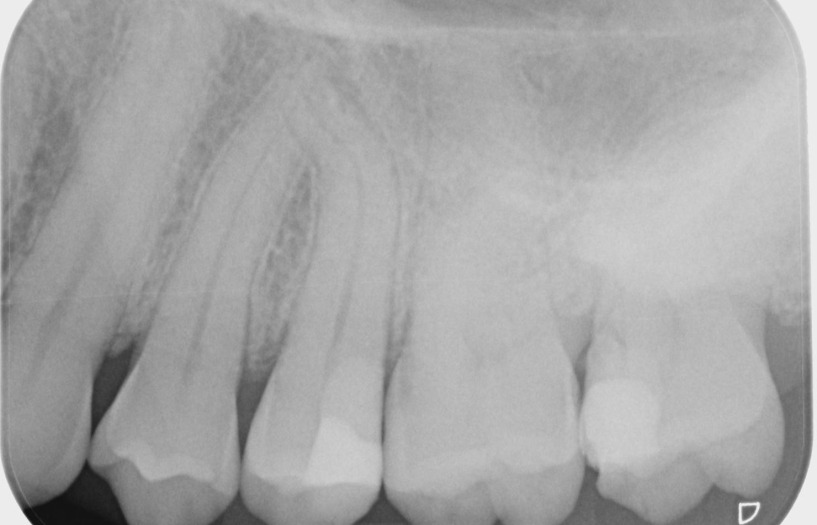

Werfen Sie einen Blick auf das Röntgenbild und seien Sie live dabei am Mittwoch, den 28. Januar 2026 ab 18:00 Uhr.

• 36-jährige weibliche Patientin; stellte sich mit Kälteempfindlichkeit und Beschwerden beim Kauen vor

• Fluoreszenz mit Flexion Twin Blue unauffällig, Taschentiefen im Normbereich

• Perkussion und Palpation negativ, Vitalitätsprüfung positiv

• Zähne 24 und 26 ebenfalls vitalitätspositiv auf Kälte